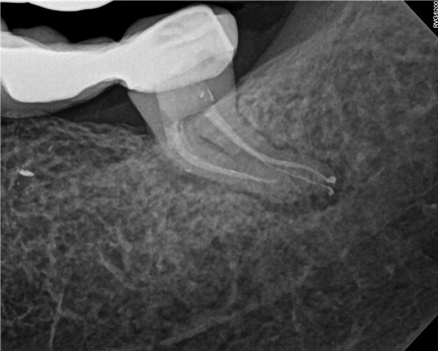

In the first case study, a young female patient was told she had a tooth (tooth No. 2, Figure 3) that should be extracted due to extensive bone loss. Using CBCT, the clinician was able to identify a large lateral canal within the palatal root. Despite the bone loss, the patient was eager to save her tooth. He offered to treat the tooth with the broad-spectrum acoustic technology. As shown in Figure 4, the preparation space was much smaller, which he was able to obturate efficiently. In addition, the small pinpoint of sealer in the middle of the palatal root indicated that the palatal lateral canal had been addressed (Figure 5). In the clinician's opinion, this area was likely the primary source of much of the bone loss.

Figure 6 through Figure 8 demonstrate that, 5 months after the procedure, complete healing had occurred, notably on the distal, where the probing had resolved to 2 mm. The patient then had a crown placed by her general dentist. Given her positive experience with the technology, she was eager to return as needed for continued follow-up.

Fig 4. Case 1: CBCT showed a large lateral canal within the palatal root (Fig 3). There was a small preparation space, which was efficiently obturated (Fig 4). A small pinpoint of sealer in the middle of the palatal root indicated that the palatal lateral canal had been addressed (Fig 5). After 5 months, CBCT demonstrated complete healing (Fig 6), notably on the distal, where probing had resolved to 2 mm. Radiographic images were taken immediately postoperatively (Fig 7) and 5 months postoperatively (Fig 8).

Fig 5. Case 1: CBCT showed a large lateral canal within the palatal root (Fig 3). There was a small preparation space, which was efficiently obturated (Fig 4). A small pinpoint of sealer in the middle of the palatal root indicated that the palatal lateral canal had been addressed (Fig 5). After 5 months, CBCT demonstrated complete healing (Fig 6), notably on the distal, where probing had resolved to 2 mm. Radiographic images were taken immediately postoperatively (Fig 7) and 5 months postoperatively (Fig 8).

Fig 6. Case 1: CBCT showed a large lateral canal within the palatal root (Fig 3). There was a small preparation space, which was efficiently obturated (Fig 4). A small pinpoint of sealer in the middle of the palatal root indicated that the palatal lateral canal had been addressed (Fig 5). After 5 months, CBCT demonstrated complete healing (Fig 6), notably on the distal, where probing had resolved to 2 mm. Radiographic images were taken immediately postoperatively (Fig 7) and 5 months postoperatively (Fig 8).

Fig 7. Case 1: CBCT showed a large lateral canal within the palatal root (Fig 3). There was a small preparation space, which was efficiently obturated (Fig 4). A small pinpoint of sealer in the middle of the palatal root indicated that the palatal lateral canal had been addressed (Fig 5). After 5 months, CBCT demonstrated complete healing (Fig 6), notably on the distal, where probing had resolved to 2 mm. Radiographic images were taken immediately postoperatively (Fig 7) and 5 months postoperatively (Fig 8).

Fig 8. Case 1: CBCT showed a large lateral canal within the palatal root (Fig 3). There was a small preparation space, which was efficiently obturated (Fig 4). A small pinpoint of sealer in the middle of the palatal root indicated that the palatal lateral canal had been addressed (Fig 5). After 5 months, CBCT demonstrated complete healing (Fig 6), notably on the distal, where probing had resolved to 2 mm. Radiographic images were taken immediately postoperatively (Fig 7) and 5 months postoperatively (Fig 8).